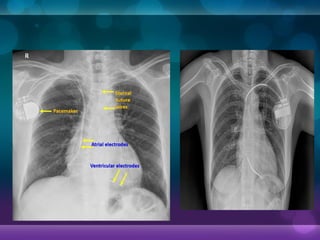

• Defining the type of device is accomplished by

• Ordering chest x-rays if no other data are available,